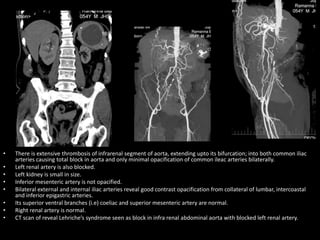

• There is extensive thrombosis of infrarenal segment of aorta, extending upto its bifurcation; into both common iliac

arteries causing total block in aorta and only minimal opacification of common ileac arteries bilaterally.

• Left renal artery is also blocked.

• Left kidney is small in size.

• Inferior mesenteric artery is not opacified.

• Bilateral external and internal iliac arteries reveal good contrast opacification from collateral of lumbar, intercoastal

and inferior epigastric arteries.

• Its superior ventral branches (i.e) coeliac and superior mesenteric artery are normal.

• Right renal artery is normal.

• CT scan of reveal Lehriche’s syndrome seen as block in infra renal abdominal aorta with blocked left renal artery.